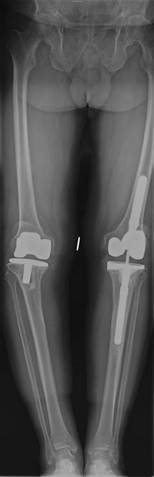

Illustration 8 for Ace FRCS Orthopaedics: Oxford University Press Adult Pathology Viva

๐Ÿ” Click to enlarge

Clinical Radiograph / Orthopedic Image

What implants do you use for revision total knee replacements?

[You are passed a hinged prosthesis] What are the benefits and disadvantages of this type of component?

If you were to revise a unicompartmental knee replacement what implant would you choose?

If you had a patient with a posterior cruciate ligament (PCL) sacrificing knee with a complete medial collateral ligament disruption and dislocation what implant choice might you make?

What implant do you use for revision total knee replacements (TKRs)?

[ This question is aimed at exploring your understanding of pre-operative planning based on the individual requirements of the clinical case.] The range of implants or system I use would depend on the clinical situation: primary TKR, post stabilized, super-stabilized, rotating hinge, with stems ยฑ augments, tumour prosthesis. Whenever faced with a revision situation it is also prudent to consider both amputation and arthrodesis as options.

[You are passed a hinged prosthesis.] What are the benefi ts and disadvantages of this type of component?

These implants are used in ligament insuffi ciency and/or cases with major bone loss. The problems with increasingly constrained implants are transmission of high forces across the boneโ€“cementโ€“ implant interface which can lead to premature loosening.

If you where to revise a unicompartmental knee replacement what implant would you choose?

Ideally I would use a primary TKR implant. If there has been some tibial loosening and bone loss, a stemmed implant possibly with augments may be required.

If you had a patient with a posterior cruciate ligament (PCL) sacrifi cing knee with a complete medial collateral ligament disruption and dislocation what implant choice might you make?

Most likely I would require a rotating hinge stemmed system.